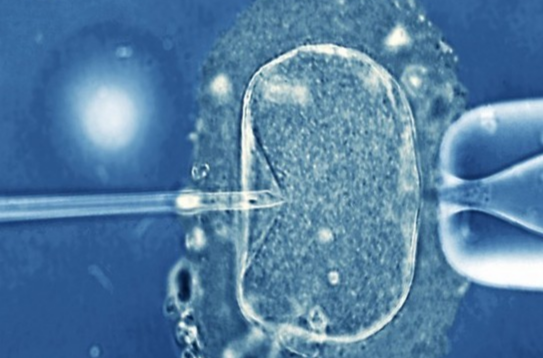

北京作为全国的医疗中心,拥有多家技术领先的试管医院。2025年,试管双胞胎的费用成为许多家庭关注的焦点。本文将从费用构成、医院选择、双胞胎成功率、支付方式以及注意事项五个方面,为您全面解析北京试管双胞胎的最新费用情况,助您更好地规划生育计划。

试管双胞胎的费用因医院和个人情况而异,以下是2025年北京试管双胞胎的详细费用构成: